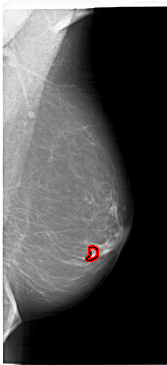

FILE: A_1621_1.RIGHT_MLO.OVERLAY

TOTAL_ABNORMALITIES 1

ABNORMALITY 1

LESION_TYPE CALCIFICATION TYPE PLEOMORPHIC DISTRIBUTION CLUSTERED

LESION_TYPE MASS SHAPE LOBULATED MARGINS ILL_DEFINED

ASSESSMENT 4

SUBTLETY 3

PATHOLOGY MALIGNANT

TOTAL_OUTLINES 1

BOUNDARY